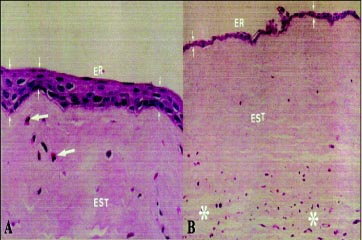

Descrição dos cortes histológicos dos olhos controle

No epitélio corneano, composto, em média, por quatro a cinco camadas celulares, percebeu-se claramente a regularidade de sua espessura. Tratava-se de epitélio pavimentoso não queratinizado, cujas células variaram de morfologia nas três camadas: camada basal, de células mais "alongadas"; camada média de células poliédricas, e camada superficial, de células achatadas (Fig. 3A).

A membrana basal foi vista como uma fina linha logo abaixo da camada basal, sendo melhor percebida nos cortes histológicos corados pelo PAS (Fig. 3A).

Quatro a cinco camadas de células poliédricas foram percebidas no epitélio conjuntival. Contaram-se, em média, 10 células caliciformes por campo de grande aumento (400X), dispersas superficialmente entre as demais células epiteliais. Apesar do mesmo número de camadas, o epitélio conjuntival mostrou-se menos espesso que o epitélio corneano (Fig. 3B).

Na região límbica, percebeu-se aumento da espessura do epitélio, que passou a apresentar, em média, 6 a 7 camadas de células. As células epiteliais do limbo não apresentaram, em suas camadas, uma mudança de morfologia tão evidente quanto às células do epitélio corneano, caracterizando um padrão intermediário entre o epitélio conjuntival e o epitélio corneano. Não se observaram células caliciformes. A transição desses epitélios foi facilmente percebida pela mudança de características da disposição das células de cada epitélio (Fig. 3C).

Um tecido conjuntivo frouxo permeado de vasos foi percebido logo abaixo do epitélio conjuntival, estendendo-se em direção ao limbo. À medida que se aproximou da córnea, foi-se tornando menos espesso, até que se deteve um pouco antes da transição córneo-escleral. Parte do epitélio límbico se apoiava diretamente sobre o leito córneo-escleral, sem o aporte vascular (Fig. 3D).

A uniformidade da espessura estromal, da compactação e padrão de suas lamelas e da densidade das células estromais nos cortes histológicos foi evidente (Fig. 3A,C,D). Não foram vistos vasos no estroma da córnea ou células inflamatórias. A transição do estroma corneano para a esclera foi facilmente distinguida pela característica disposição das fibras de cada tecido. Essa transição se deu de forma oblíqua, sendo que, mais superficialmente, ela foi mais anteriorizada (voltada em direção ao centro da córnea) e, profundamente, o oposto (Fig. 3D). A membrana de Descemet estava presente sobre o endotélio, que era formado por uma camada de células.

Descrição dos cortes histológicos no 1º dia

O epitélio corneano estava ausente nas três técnicas. A membrana basal foi vista no PAS como uma fina linha contínua (Fig. 4D). O epitélio límbico foi apenas parcialmente removido na T1, notando-se ausência das camadas superficiais, com suas células achatadas em todos os quadrantes corneanos (Fig. 4A). Na T2, o epitélio límbico foi mais amplamente removido. Em alguns quadrantes corneanos esse epitélio foi totalmente removido, sendo que, em outros, houve persistência da camada basal, apenas (Fig. 4B). Não houve um quadrante específico onde as células basais do epitélio límbico mais persistiram. Na T3, a localização límbica da dissecção lamelar foi claramente percebida em todos os cortes histológicos. Nas bordas da região removida, observou-se uma margem anterior no estroma corneano íngreme e uma margem posterior, mais oblíqua. A profundidade de tecido removido foi semelhante nas secções observadas, alcançando entre um terço e meia espessura da córnea e esclera (Fig. 4C).

Na T1, o epitélio conjuntival próximo à região límbica foi removido, estando presente apenas mais distalmente; abaixo, o tecido conjuntivo frouxo foi preservado. Na T2, o epitélio conjuntival estava ausente, bem como a parte superficial do conjuntivo frouxo subepitelial. Na T3, foi evidente que na área dissecada todos os tecidos acima (epitélios corneano, límbico, conjuntival e conjuntivo frouxo) foram removidos.

A resposta inflamatória no estroma corneano foi ausente nos três grupos, assim como não ocorreu vascularização corneana e/ou resposta fibroblástica. Descemet e endotélio não apresentaram alterações (Fig. 4A, B, C).